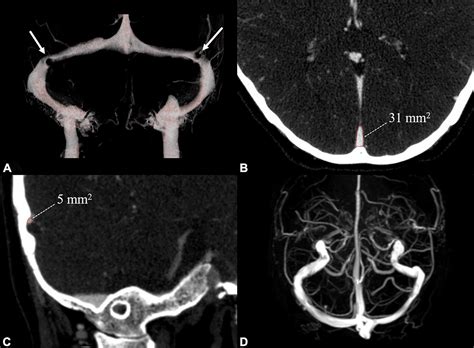

Magnetic Resonance Venography (MRV) Uses magnetic resonance imaging to visualize the venous sinuses and detect any abnormalities.

Computed Tomography Venography (CTV) Uses computed tomography to create detailed images of the venous sinuses.

Digital Subtraction Angiography (DSA) Provides a detailed view of the blood vessels and can help identify the exact location and extent of the stenosis.

These imaging tests are crucial for confirming the diagnosis and planning appropriate treatment.